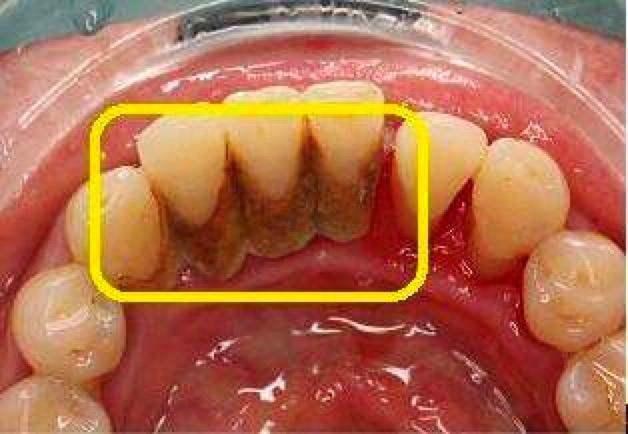

口腔是一个充满各种微生物的潮湿环境,其中包含一种粘附于牙齿表面的微生物群——菌斑。牙菌斑就像是由不同细菌组成的“细菌社区”,它们依附在牙齿表面、牙缝间等部位,并且难以被水冲去或者漱掉,只能通过专门的洗牙器械清除。

别看牙菌斑肉眼看不见,但危害可不小。当它分解唾液中的糖,分解产生酸时,就会蛀牙;当它堆积在牙齿上,慢慢会钙化出牙结石。假如牙齿是一棵树,牙周是培育牙齿的土壤,而牙结石就是占据良好土壤的石头。一旦牙结石形成,就会压迫牙龈,造成牙龈萎缩、肿胀甚至发炎的情况。可见,牙菌斑和牙结石这类口腔杀手,不容忽视!